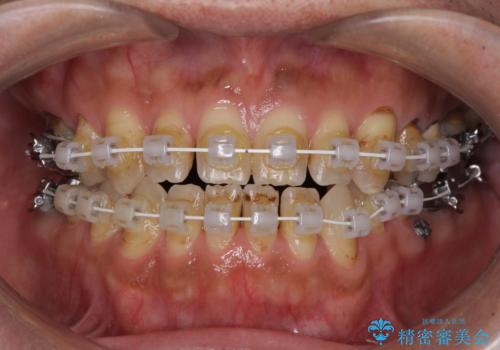

- 審美装置

奥歯には抜歯が必要な歯があったため、事前に抜歯を行い、その後ワイヤー装置にて治療を開始しました。

前歯の反対咬合が改善する過程では、奥歯が咬みにくくなるため、食事では辛い思いをされていたようです。